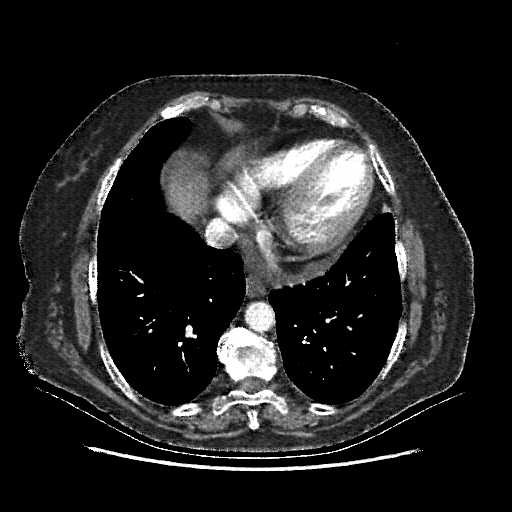

Original VENOUS CT scan

No window - Raw intensity values

Lung window (WL -600, WW 1500 β†’ Low βˆ’1350, High +150)

Mediastinum window (WL 40, WW 400 β†’ Low βˆ’160, High +240)